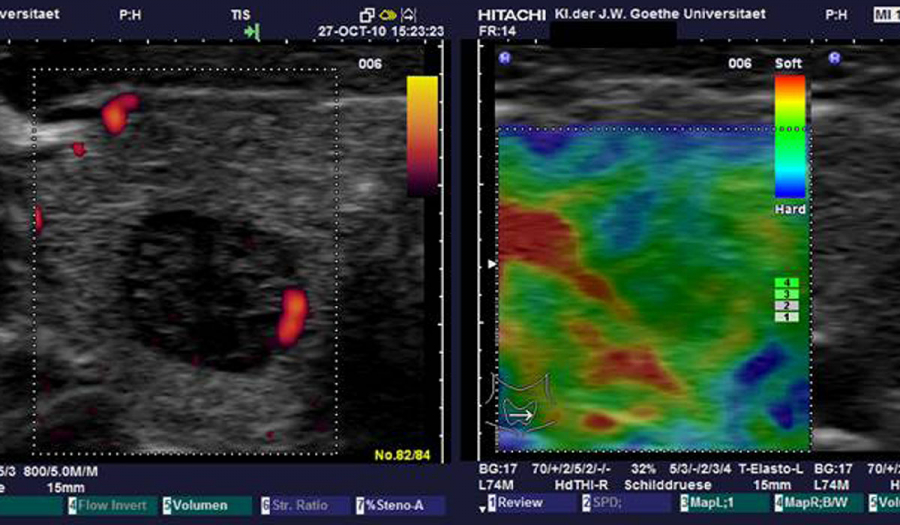

Еластографія – один з найбільш сучасних методів ультразвукової діагностики, який дозволяє оцінити пружність тканин. Це корисний інструмент для дослідження поверхнево розташованих органів (молочних і слинних залоз, лімфовузлів, м’яких тканин), а також оцінки ступінь фіброзу при хронічних захворюваннях печінки.